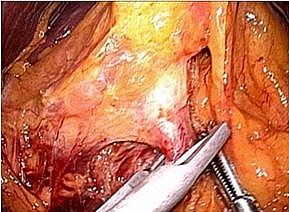

腹腔鏡下胃切除術の実際

全身麻酔下で手術を行います。まず腹腔内(腹腔:お腹の壁と臓器との間の空間)に炭酸

ガスを入れて膨らませ、お臍からカメラ(腹腔鏡)を挿入します。同時に手術操作に用い

る器具(鉗子など)を挿入するための5〜10mmの小さな穴を左右に4カ所開けます。そ

して腹腔鏡で撮ったお腹の中の様子をモニターに映し出して、胃切除や周囲のリンパ節

の切除を行います。開腹手術では見えにくかった細い血管や神経まで見えて繊細な手術

操作が可能です。

完全腹腔鏡下幽門側胃切除術

(胃の出口(幽門)を含めて胃の下方約2/3を切除する術式)

胃の全体 十二指腸離断

左胃動脈 胃切離